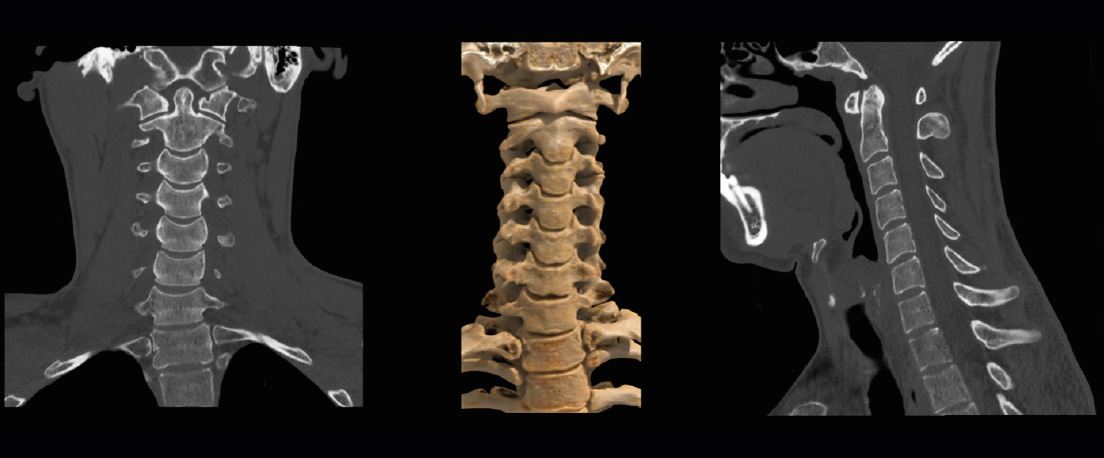

скринінгу раку легенів, ми використовуємо його для стандартного зображення грудної клітки. Ми також використовуємо його для візуалізації кісток, тому що ми отримуємо набагато менше артефактів і доза набагато нижча. Якщо це хребет чи пазухи, або якщо ми шукаємо перелом стегна, ми використаємо SilverBeam».

Сканування шийного відділу хребта SilverBeam. На зображеннях видно зменшені артефакти в області плечей.

SilverBeam

Фільтр для КТ-систем Aquilion, який містить срібло для вибіркової оптимізації енергії

променя. Він видаляє фотони низької енергії зі спектру променя, які не впливають на якість зображення, але збільшують дозу та

розсіювання. У поєднанні з технологією Advanced intelligent Clear IQ Engine (AiCE) Canon Medical цей енергетичний фільтр, що формує промінь, може використовувати потужність

штучного інтелекту для забезпечення високої

якості зображення та низького рівня шуму для спеціальних програм.